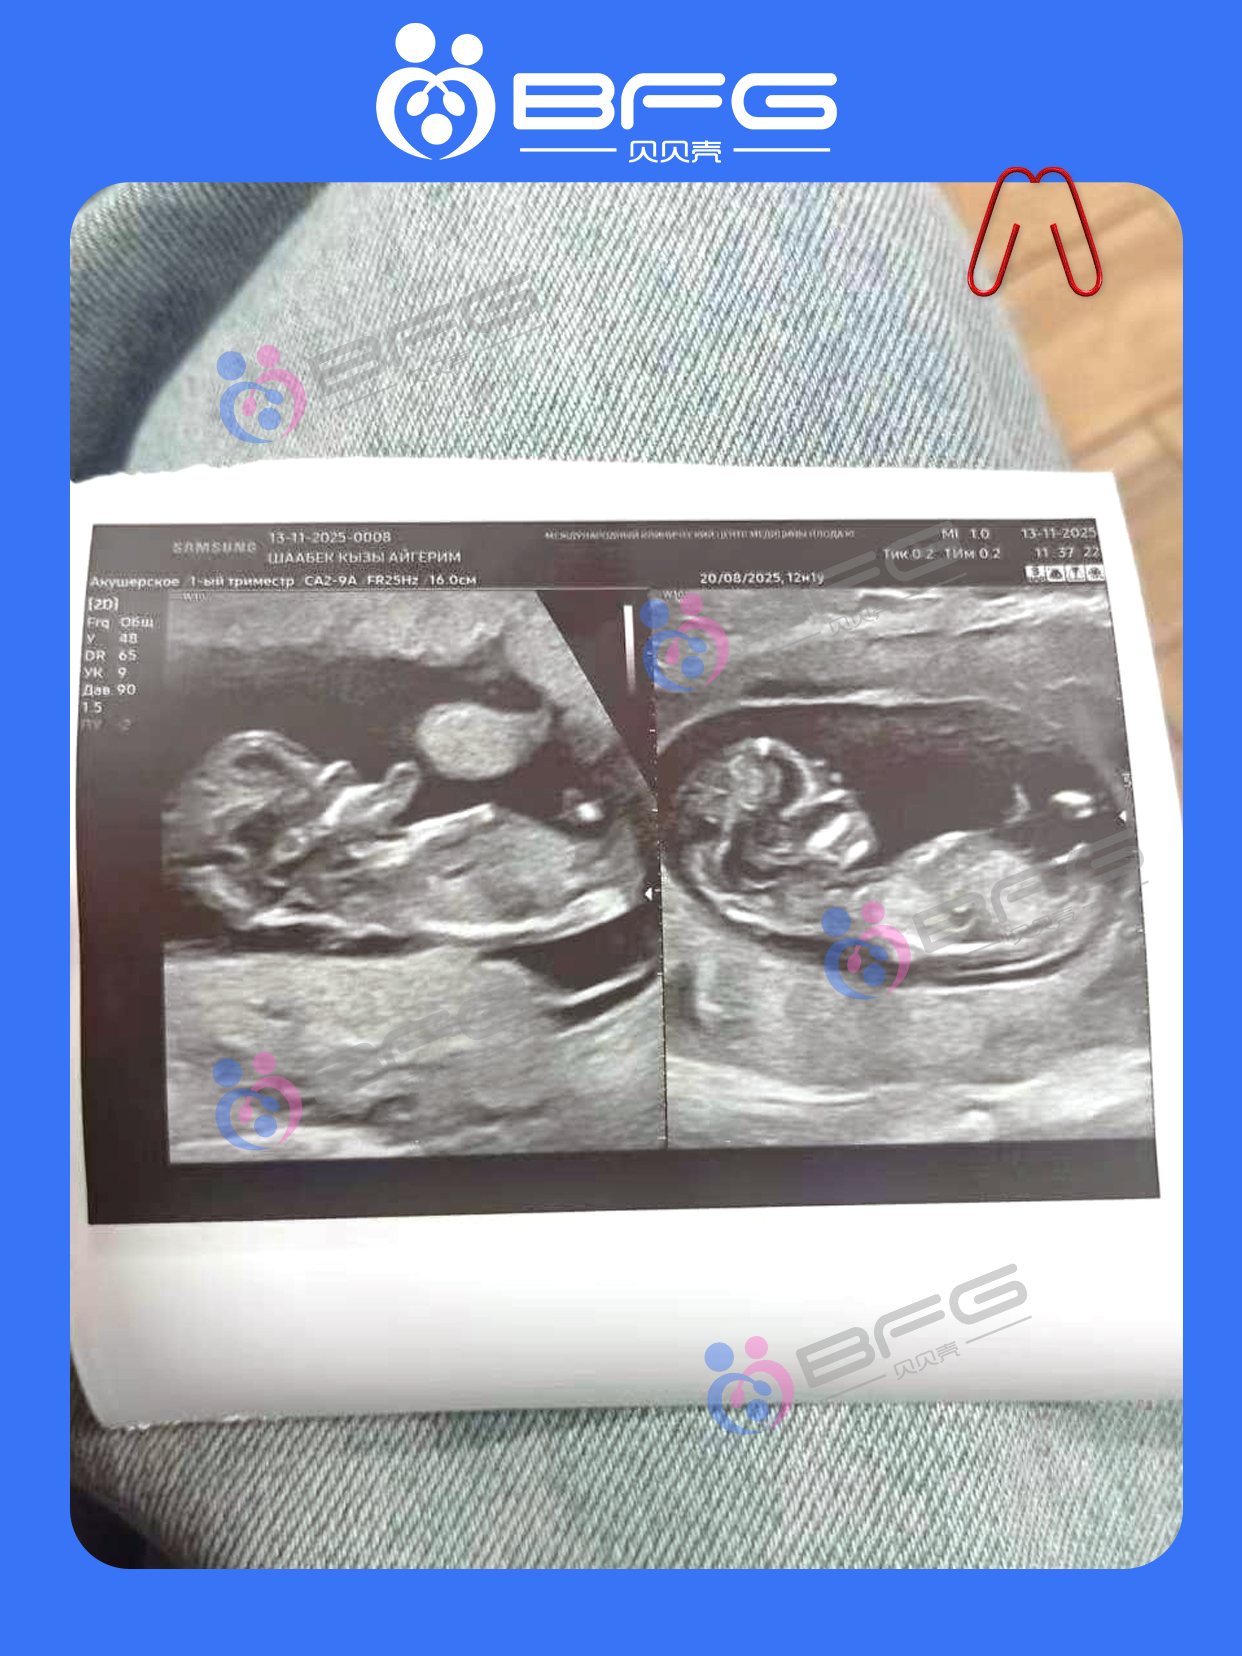

[爱心]❥(^_-)妈妈移植后一路顺利,在BFG的呵护下正式建档啦,12周双胎![庆祝]